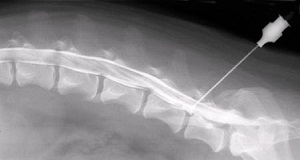

Миелография (контрастная спондилография) - метод рентгенографического исследования спинного мозга с использованием контрастного вещества. При обычном обзорном рентгене на снимке видны контуры только костной ткани позвоночника. Применение контрастного вещества позволяет увидеть также контуры нервных тканей - спинного мозга и спинномозговых нервов.

Проведение миелографии

В качестве контрастного вещества чаще всего используется омнипак (ойгексол). Препарат вводится путем прокола оболочки спинного мозга (как, например, при эпидуральной анестезии). Процедура проводится под наркозом, в стерильных условиях операционной. Контрастное вещество может вводиться в поясничном отделе позвоночника или в области большого затылочного отверстия (субокципитальная пункция), часто показано одновременное введение контраста и люмбально (в области поясницы) и окципитально (в области затылочного отверстия). Субокципитальная пункция более опасна - есть вероятность (порядка 1-2%) повреждения сосуда, что приводит к отеку спинного мозга и дыхательному и сердечно-сосудистому параличу.

В некоторых случаях проведение миелографии может привести к усилению компрессии (давления) на спинной мозг, и ухудшению неврологических симптомов, поэтому проведение такой диагностики требует четких показаний и грамотного подхода.